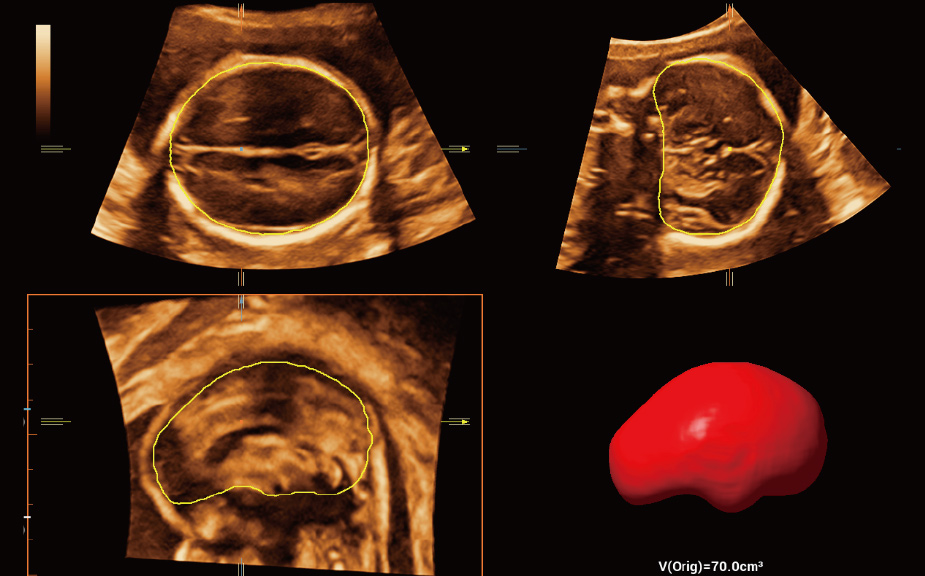

Scenario-oriented Full-stack Intelligence

The innovative Smart Scene 3D solution enables automated identification of tissue characteristics and delivers organ-specific diagnosis with full-stack intelligence throughout the entire procedure. This innovation reduces dependence on clinical skills, while elevating diagnostic accuracy, confidence, and efficiency.